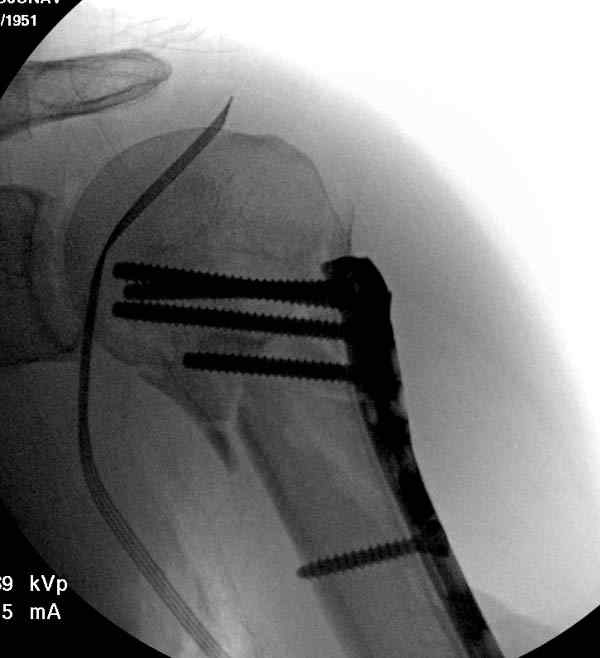

Здесь пример открытой репозиции 57 летнего с переломом плеча (1,2)  смещение обнаружено на  интероперационном снимке. При нормальной прямой проекция (3) угловое смещение обнаружили в аксиальной проекции (4)

После устранения смещения пластина установлена выше (5,6,7) и финальные снимки (8,9,10)